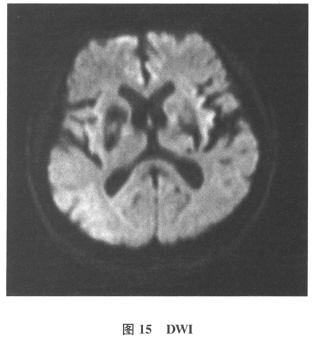

[单选题]患者男,61岁。因“发作性头晕2年,加重伴记忆力下降、走路不稳3月余”就诊。查体:BP140/70mmHg;意识清楚,构音障碍,近期记忆力及远期记忆力

[多选题]患者男,61岁。因“发作性头晕2年,加重伴记忆力下降、走路不稳3月余”就诊。查体:BP140/70mmHg;意识清楚,构音障碍,近期记忆力及远期记忆力